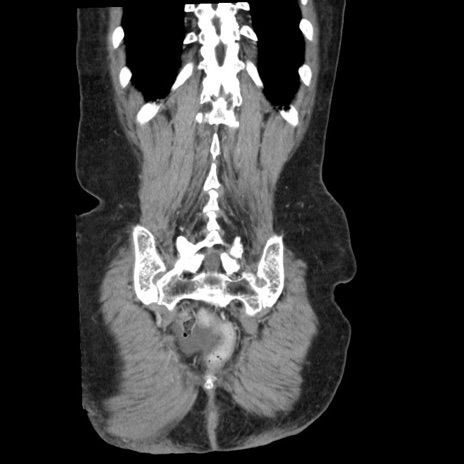

矢状断像

【症例】80歳代女性

【主訴】腹痛

【現病歴】8時間前から腹痛あり来院。

【既往歴】糖尿病、脂質異常症、子宮体癌にて子宮全摘術

【身体所見】意識清明・会話良好だが腹痛で苦悶様、全腹部にわたって反跳痛と圧痛あり

【データ】WBC 13600、CRP 0.14、LDH 224、CK 90